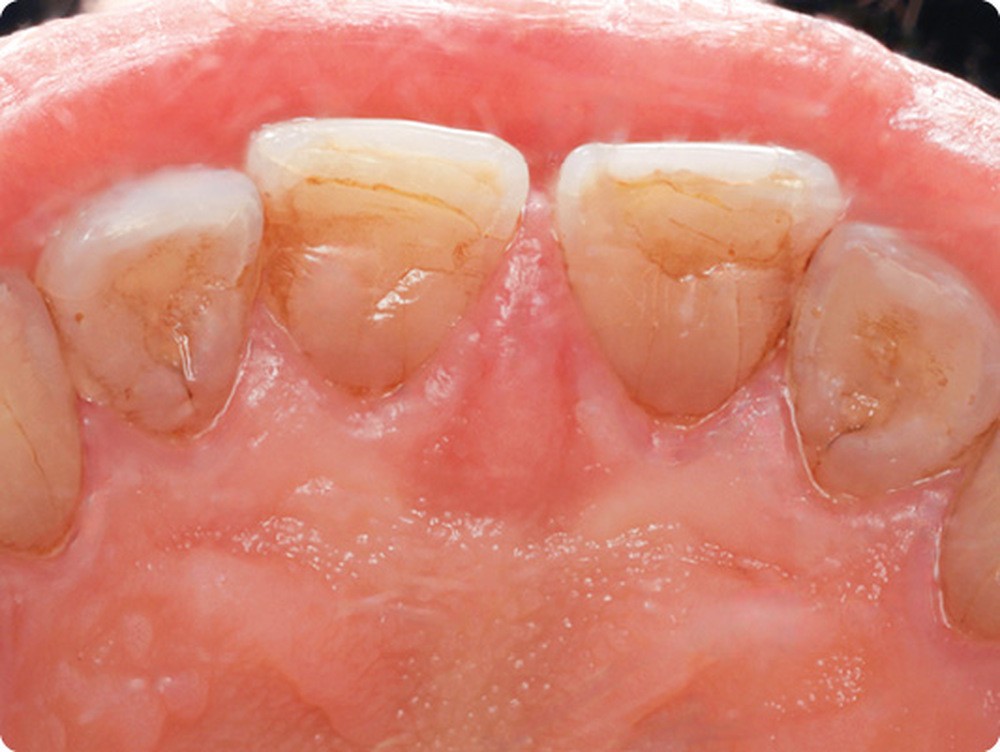

• Dans la région palatine médiane antérieure, on observait une tuméfaction limitée à la papille palatine. Cette dernière, douloureuse à la palpation, était recouverte par une muqueuse érythémateuse. Les dents 11 et 21 étaient vivantes et elles ne présentaient pas d’atteinte parodontale active.